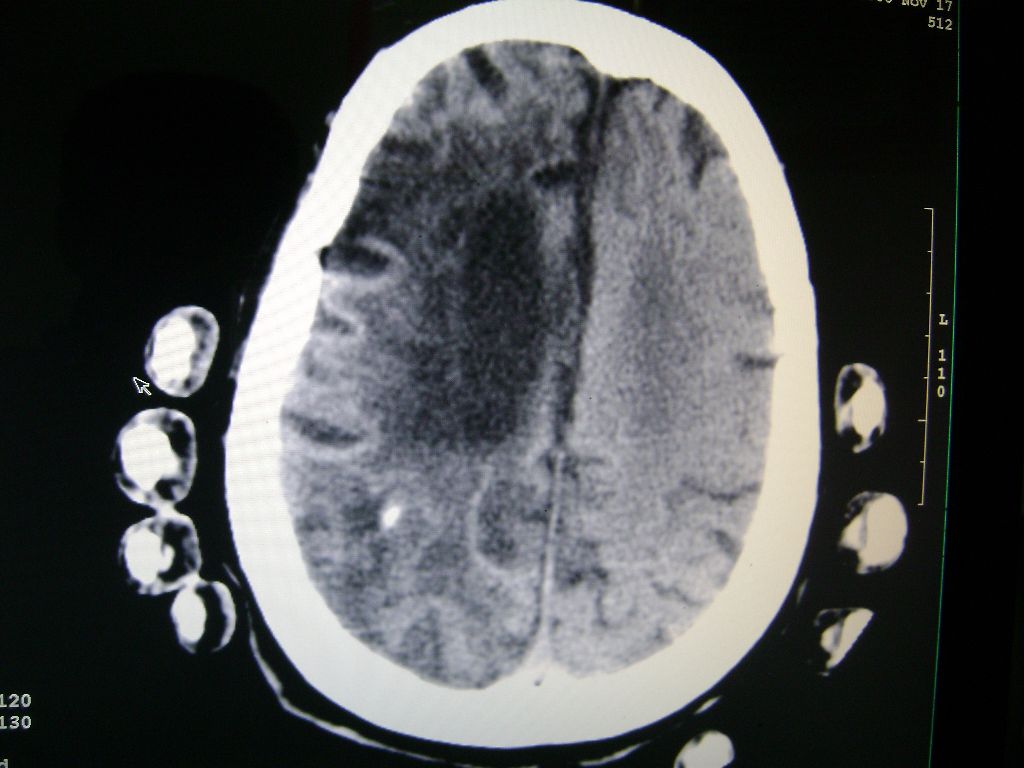

f 77 昏迷不醒

右侧额颞枕顶叶脑软化灶,脑萎缩,大脑中动脉壁钙化。

右脑软化灶,考虑再次梗塞,高密度灶出血?钙化?。。。量ct值,改窗宽,位

右脑软化灶,考虑再次梗塞,右顶叶高密度影不像是出血,密度很高,建议量ct值!

右侧半球陈旧性卒中,不除外伴有新病灶,左额叶梗塞,双侧大脑中动脉钙斑

右侧额颞枕顶叶脑软化灶,脑萎缩,大脑中动脉壁钙化。不支持出血(密度高,边界清且局限)顶枕区似有新发梗塞,建议核磁

1)右侧额颞枕顶叶脑软化灶;其内高密度影,多为钙化灶。2)脑萎缩。3)大脑中动脉钙化。

再次脑梗死,右侧额颞枕顶叶脑软化灶,高密度考虑钙化

右侧陈旧脑梗塞伴脑萎缩。脑内点状钙化。大脑中动脉壁钙化灶。无出血灶。

1)右侧额颞枕顶叶脑软化灶并钙化灶可能。2)脑萎缩。3)大脑中动脉钙化。 -